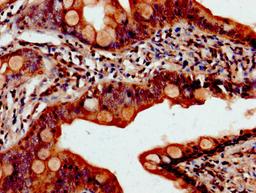

IHC image of CSB-PA861141HA01HU diluted at 1:800 and staining in paraffin-embedded human small intestine tissue performed on a Leica BondTM system. After dewaxing and hydration, antigen retrieval was mediated by high pressure in a citrate buffer (pH 6.0). Section was blocked with 10% normal goat serum 30min at RT. Then primary antibody (1% BSA) was incubated at 4°C overnight. The primary is detected by a biotinylated secondary antibody and visualized using an HRP conjugated SP system.